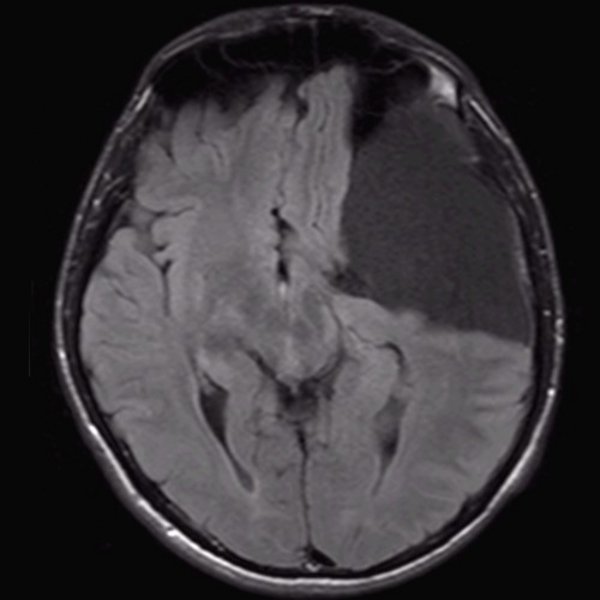

Arachnoidalzyste

Arachnoidalzyste T1 transversal

Arachnoidalzyste T2 transversal